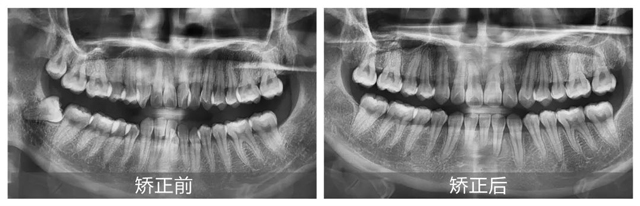

经过详细面诊,并根据口扫、CBCT检查结果显示,邓女士主要面临的问题有上颌牙列中度拥挤、下颌牙列重度拥挤,并且有一颗下切牙由于长期的拥挤已经出现牙周炎症状。

郝璐医生指出,因为牙齿过于紧密,邓女士的下前牙排列错位,形成了咬合创伤,同时伴有牙槽骨吸收和牙龈萎缩的情况。此外,上颌左侧切牙和右侧尖牙反颌,造成了上下颌牙弓不对称,上下颌中线不一致,前牙深覆合。这些情况在邓女士张口说话时很容易就能注意到,严重影响了面部美观。

郝璐医生表示,针对邓女士的情况,治疗的主要目标是解除牙列拥挤情况,调整反颌关系,消除咬合创伤,从而改善整体口腔健康状况。

1、为缓解下颌重度拥挤,首先拔除下颌前牙错位的一颗牙齿,避免歪牙继续损伤牙槽骨和牙龈。

2、采用金属矫治器配合上颌片切技术,为排齐上牙腾出少量空间,减少拔牙量,并排齐整平上下牙列,纠正反颌现象。

3、并使用平面导板技术打开咬合,压底下前牙,减轻前牙深覆合问题,同时调整上下中线至理想位置,笑起来更对称。

经过一年零三个月的精心矫正,在取下牙套的那一刻,邓女士不仅圆了儿时的梦想,更重拾了那份因自信笑容而带来的快乐:“这一切都是值得的,每天看着变得这么好看的牙齿,感觉自己整个人都不一样了!”